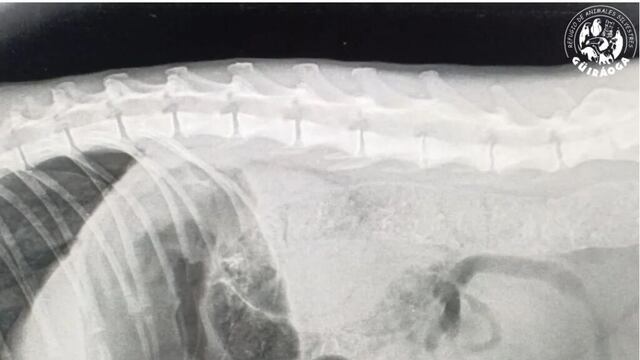

El trágico suceso tuvo lugar cuando una hembra de felino perdió la vida debido a un atropello. El responsable del accidente no respetó los límites de velocidad establecidos para las áreas protegidas. Aunque se presume que el incidente ocurrió la noche anterior, hasta el momento no se ha logrado identificar al conductor responsable.